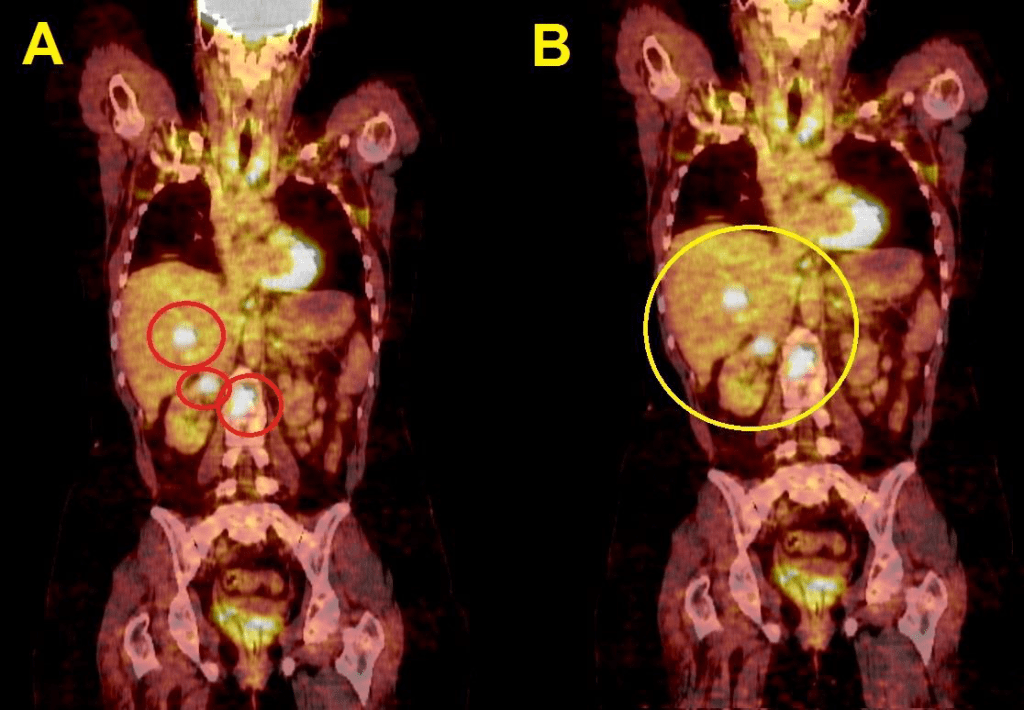

For Pet-Ct images taken for the patient pre and after the chemotherapy which shows no significant changes in the tumor distribution or size after chemotherapy.

nificant difference from the previous scan in 2004. (16- Jordanian medical services, PACS system and database store center).

The first treatment was done and a pre ablation scan was performed and showed a wide spread metastases. Six months after this image the patient was imaged again after the repetition of the previous Lu177DOTATE therapy as a second cycle treatment. The next day of the injection and here a great difference shows in the image as a great benefit and good remission in the

metastatic malignancy due to the use of Lu177DOTATE therapy which did not happen with any other treatment technique used with the patient specially the chemotherapy used before.

Figure17: Great PR appears as a result of the 177Lutitum DOTATAT radionuclide therapy after 6 months of the first cycle (16- Jordanian medical services, PACS system and database store center).